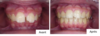

Les dents vue de face avant et après traitement appareil multi-attaches